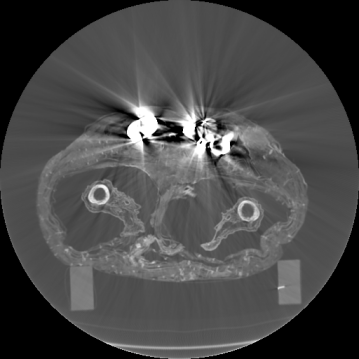

In Fig. 3a, we show one axial slice of a male mummy with indication of the regions to be segmented. Fig. 3b illustrates that metals present inside a bandaged mummy generate severe artifacts, which are not present in standard biomedical data.

In Fig. 6, we illustrate the described process using a synthetic image and a real axial frame. Note that in most slices, there exists an interior hollow space between the wrapping Bandage and Body. Detection of this region is trivial since its voxel values are the same as the air voxels in the detected exterior region. In practice, the obtained set RbsubscriptR𝑏\mathrm{R}_{b} may also include some patches from the wrap region in addition to the body patches. In the next section, we refine this result.